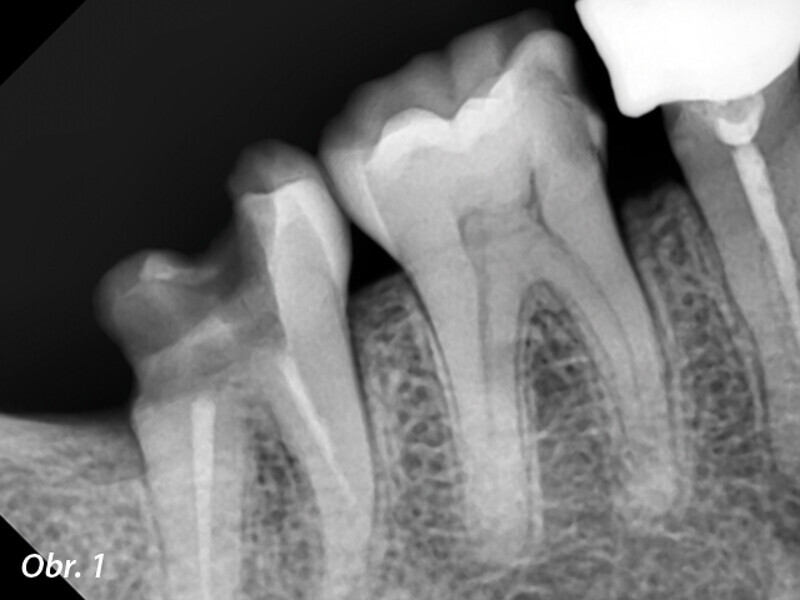

Endodontické ošetření s modulárním NiTi systémem